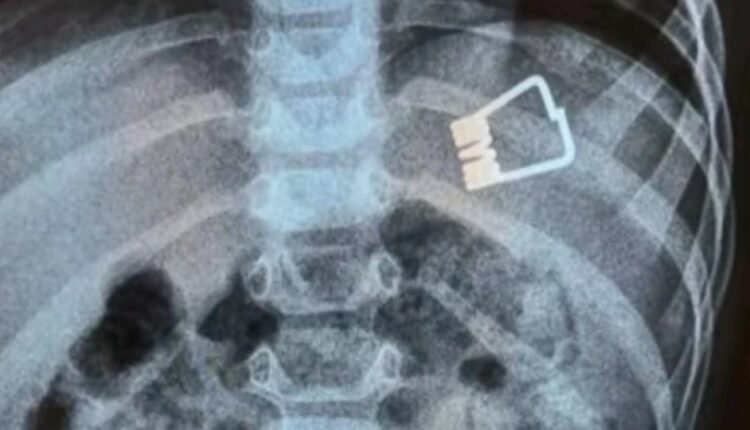

Μεγάλη περιπέτεια πέρασαν ένα αγοράκι δυο ετών και η οικογένειά του στη Λήμνο, όταν το παιδί κατάπιε ένα μανταλάκι και χρειάστηκε να διακομιστεί στο Ιπποκράτειο Νοσοκομείο στη Θεσσαλονίκη. Εκεί, οι γιατροί κατάφεραν να βγάλουν το μανταλάκι από τον οργανισμό του παιδιού χωρίς χειρουργική επέμβαση, αλλά με τη βοήθεια ενός ενδοσκοπίου τελευταίας γενιάς.

Σύμφωνα με το ρεπορτάζ της ΕΡΤ, το παιδί κατάπιε το μανταλάκι στο σπίτι του και στη συνέχεια μεταφέρθηκε με Super Puma από τη Λήμνο στη Θεσσαλονίκη, όπου το ανέλαβαν οι παιδίατροι.

«Όταν το παιδί έφτασε εδώ αμέσως κινητοποιηθήκαμε, ενημερώσαμε τους αναισθησιολόγους, είχαμε έτοιμο το χειρουργικό κρεβάτι. Το παιδί έπρεπε είναι νηστικό 6 με 8 ώρες και προβήκαμε στην αφαίρεση ενδοσκοπικά του ξένου σώματος», δήλωσε ο Ιωάννης Ξηνίας, αναπληρωτής καθηγητής Παιδιατρικής Γαστρεντερολογίας.